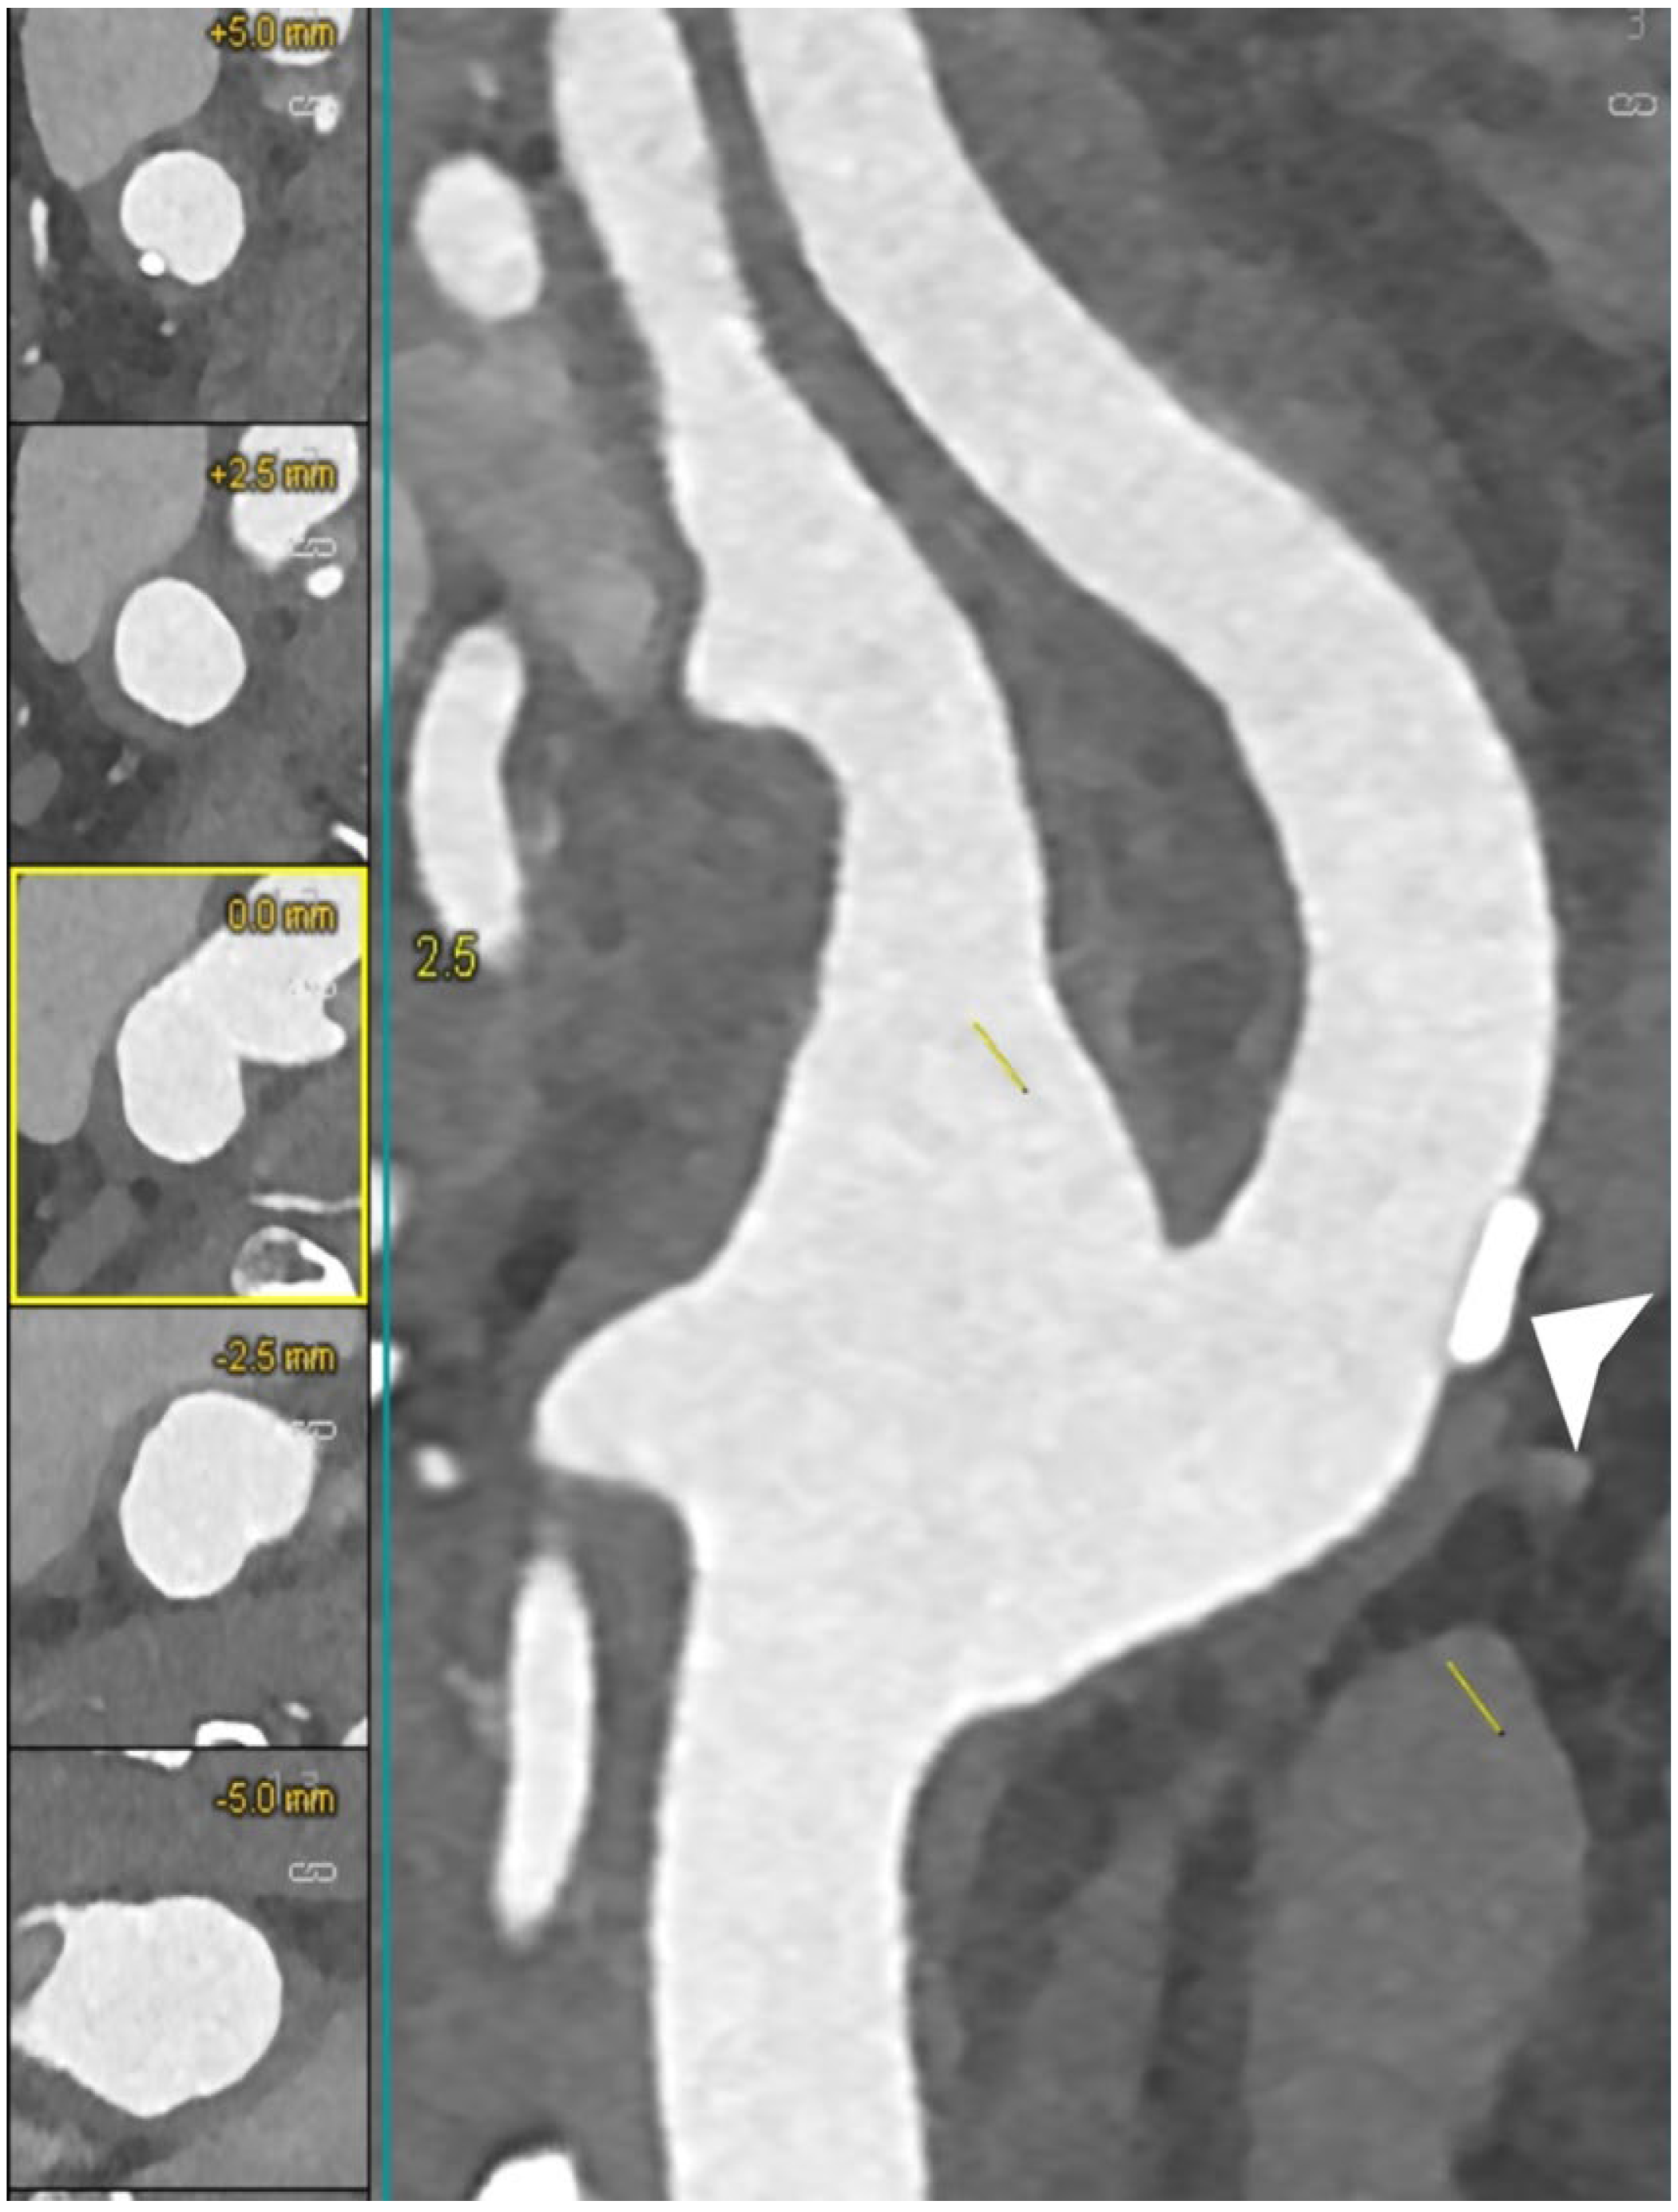

6.5. Calcium Decomposition Algorithms

- Dahal, S.; Raja, A.Y.; Searle, E.; Colgan, F.E.; Crighton, J.S.; Roake, J.; Saba, L.; Gieseg, S.; Butler, A.P.H. Components of carotid atherosclerotic plaque in spectral photon-counting CT with histopathologic comparison. Eur. Radiol. 2023, 33, 1612–1619. [Google Scholar] [CrossRef] [PubMed]

| Dahal et al. [33] | 2023 | Ex vivo (human) | 20 | Tissue analysis | FC thickness and FC area did not show significant differences between the SPCCT-derived radiological measurements and the histopathological measurements (p-value range 0.15–0.51 for FC thickness and 0.053–0.30 for FC area). |